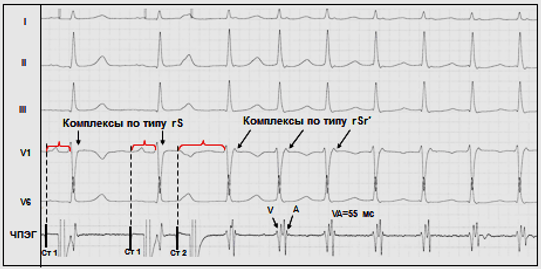

Важнейшим диагностическим признаком типичной АВУРТ является практически одновременная активация предсердий и желудочков во время аритмии, что проявляется на ЭКГ отсутствием зубцов Р вследствие их наложения на комплекс QRS и/или значениями интервалов RP<70 мс ( см ПРИЛОЖЕНИЕ Д2, а также 6). Косвенным признаком ретроградной активации предсердий во время АВУРТ может являться появление в отведении V1 положительного зубца P, наслаивающегося на конечную часть комплекса QRS, что создаёт картину, схожую с преходящей неполной блокадой правой ножки пучка Гиса - комплекс rSr ′ (6). Для уточнения временных взаимоотношений между электрическими сигналами предсердий и желудочков и подтверждения диагноза типичной АВУРТ, как правило, требуется проведение чреспищеводной или эндокардиальной записи сигналов предсердий и желудочков.

6. Индукция АВ-узловой реципрокной тахикардии (АВУРТ) одиночным экстрастимулом при проведении ЧПЭС.

Обозначения к рис 6: ЧПЭГ - чреспищеводная электрограмма предсердий; Ст1 - артефакт постоянного базисного ритма стимуляции предсердий; Ст2 - артефакт преждевременного стимула предсердий (экстрастимула). А и V - осцилляции предсердий и желудосков, соответственно на чреспищеводной электрограмме. Экстрастимул вызывает блокаду проведения по «быстрому» пути - резкое удлинение интервала Ст2-R (феномен «скачка»), что сопровождается возникновением приступа АВУРТ. Ретроградная активация предсердий во время АВУРТ проявляется характерной морфологией rSr’ в отведении V1.